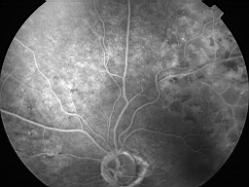

OCCLUSION DE BRANCHE DE LA VTS DE FORME ISCHEMIQUE MAJEURE